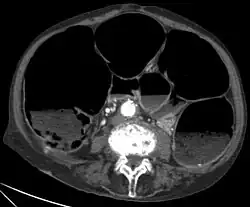

Die Diagnostik der Erkrankung ist einfach, da das Röntgenbild sehr charakteristische Zeichen aufweist. Der gesamte Dickdarm ist breit mit Luft gefüllt, vor allem der aufsteigende Teil des Dickdarmes erreicht eine Breite von oft mehr als 10 cm.

- Computertomografie des Abdomens